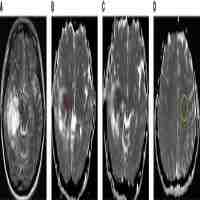

| Abstract | Isocitrate dehydrogenase mutational status defines distinct biologic behavior and clinical outcomes in low-grade gliomas. We sought to determine magnetic resonance imaging characteristics associated with isocitrate dehydrogenase mutational status to evaluate the predictive roles of magnetic resonance imaging features in isocitrate dehydrogenase mutational status and therefore their potential impact on the determination of clinical target volume in radiotherapy. Forty-eight isocitrate dehydrogenase-mutant and 28 isocitrate dehydrogenase–wild-type low-grade gliomas were studied. Isocitrate dehydrogenase mutation was related to more frequency of cortical involvement compared to isocitrate dehydrogenase–wild-type group (34/46 vs 6/24, P = .0001). Peritumoral edema was less frequent in isocitrate dehydrogenase–mutant tumors (32.6% vs 58.3% for isocitrate dehydrogenase–wild-type tumors, P = .0381). Isocitrate dehydrogenase–wild-type tumors were more likely to have a nondefinable border, while isocitrate dehydrogenase–mutant tumors had well-defined borders (66.7% vs 39.1%, P = .0287). Only 8 (17.4%) of 46 of the isocitrate dehydrogenase–mutant tumors demonstrated marked enhancement, while this was 66.7% in isocitrate–wild-type tumors (P < .0001). Choline–creatinine ratio for isocitrate dehydrogenase–wild-type tumors was significantly higher than that for isocitrate dehydrogenase–mutant tumors. In conclusion, frontal location, well-defined border, cortical involvement, less peritumoral edema, lack of enhancement, and low choline–creatinine ratio were predictive for the definition of isocitrate dehydrogenase–mutant low-grade gliomas. Magnetic resonance imaging can provide an advantage in the detection of isocitrate dehydrogenase status indirectly and indicate the need to explore new design for treatment planning in gliomas. Choline–creatinine ratio in magnetic resonance spectroscopy could be a potential more reasonable reference for the new design of delineation of target volume in low-grade gliomas. |